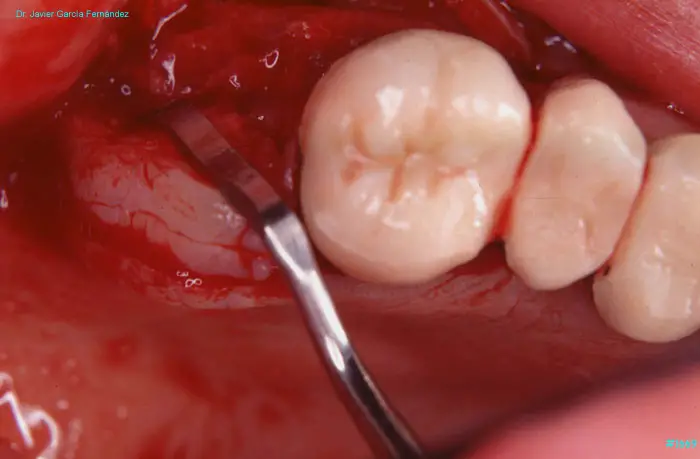

image 181